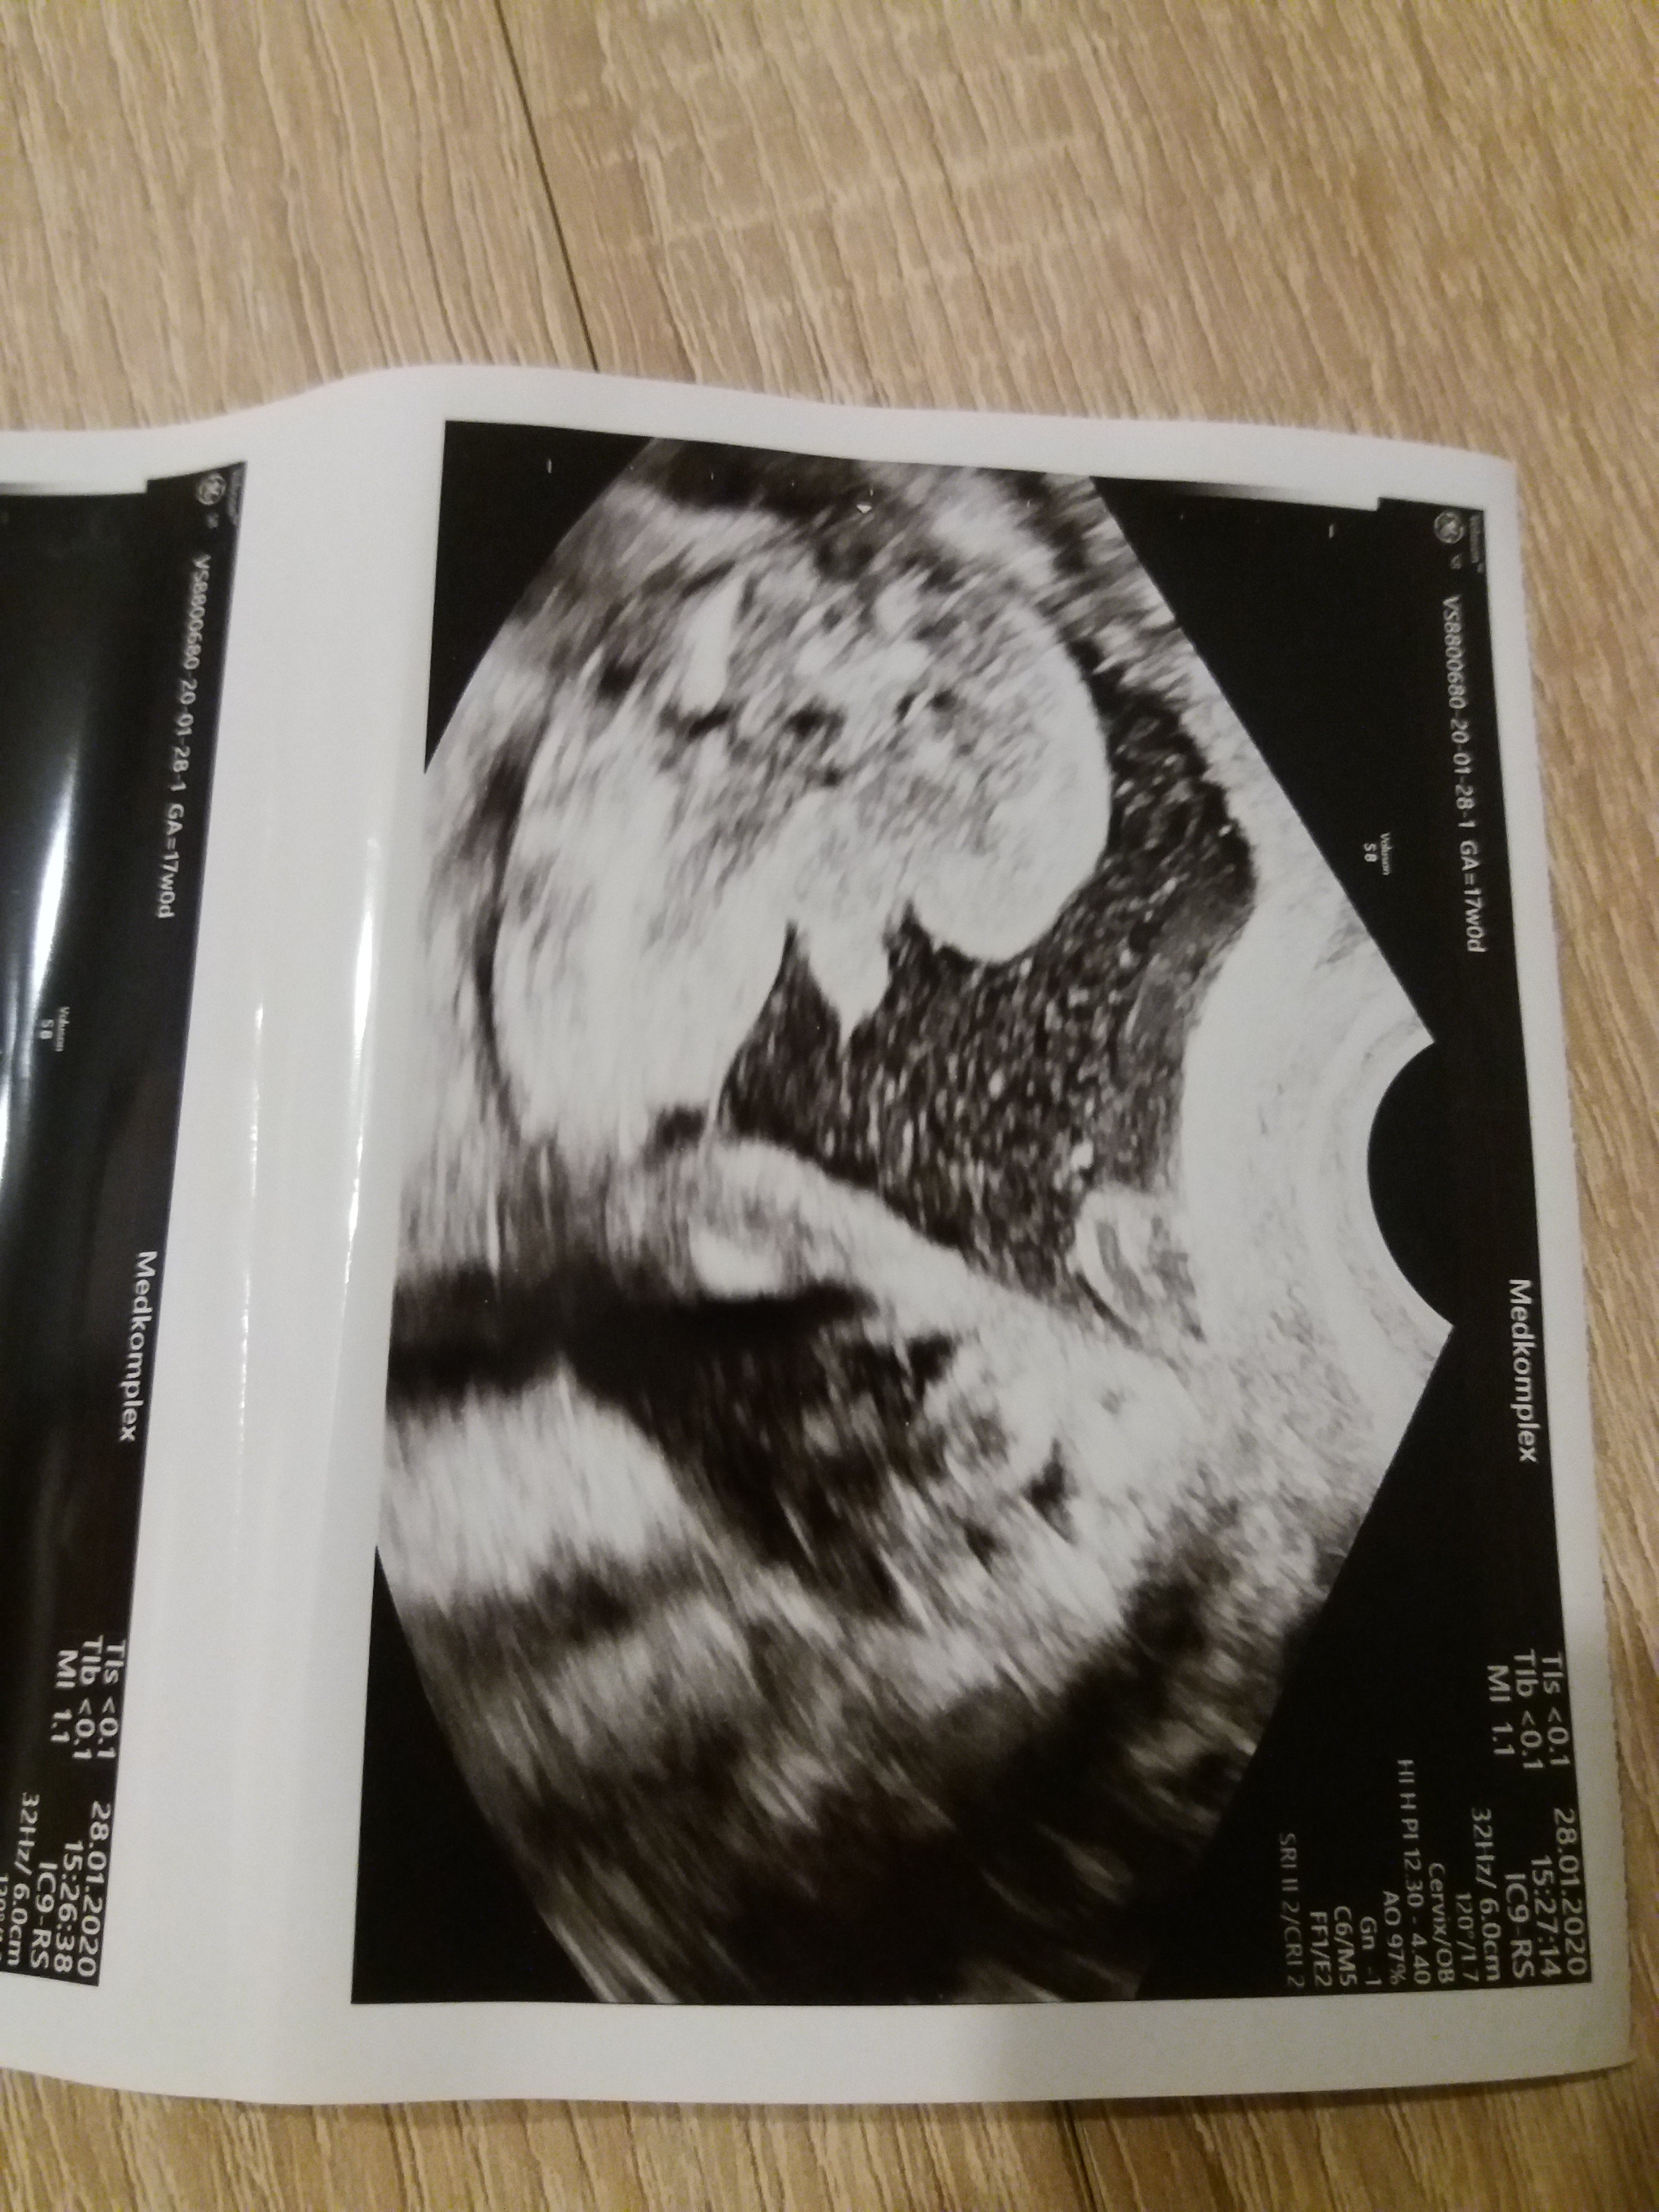

Ciężko stwierdzić. Pokaże ci moje foto z 17 tc zupełnie inne ujęcie . Z tego twojego ciężko cos obstawiać

Załączniki

• 20200128_162413.jpg

20200128_162413.jpg

1,4 MB · Wyświetleń: 1 004